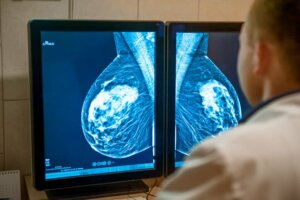

La stadiazione o la stadiazione può essere sia clinica che patologica. La scheda clinica è realizzata sulla base dei diversi studi di imaging e biopsie eseguite. Da parte sua, la determinazione patologica è possibile solo dopo l’intervento chirurgico, in cui uno specialista analizzerà il tessuto estratto.

Durante queste fasi, uno dei metodi diagnostici preferiti sono i test di imaging come la mammografia e l’ecosonografia mammaria. Anche la prognosi è generalmente buona nella maggior parte dei casi, a seconda della presenza di recettori ormonali e della produzione della proteina HER2.